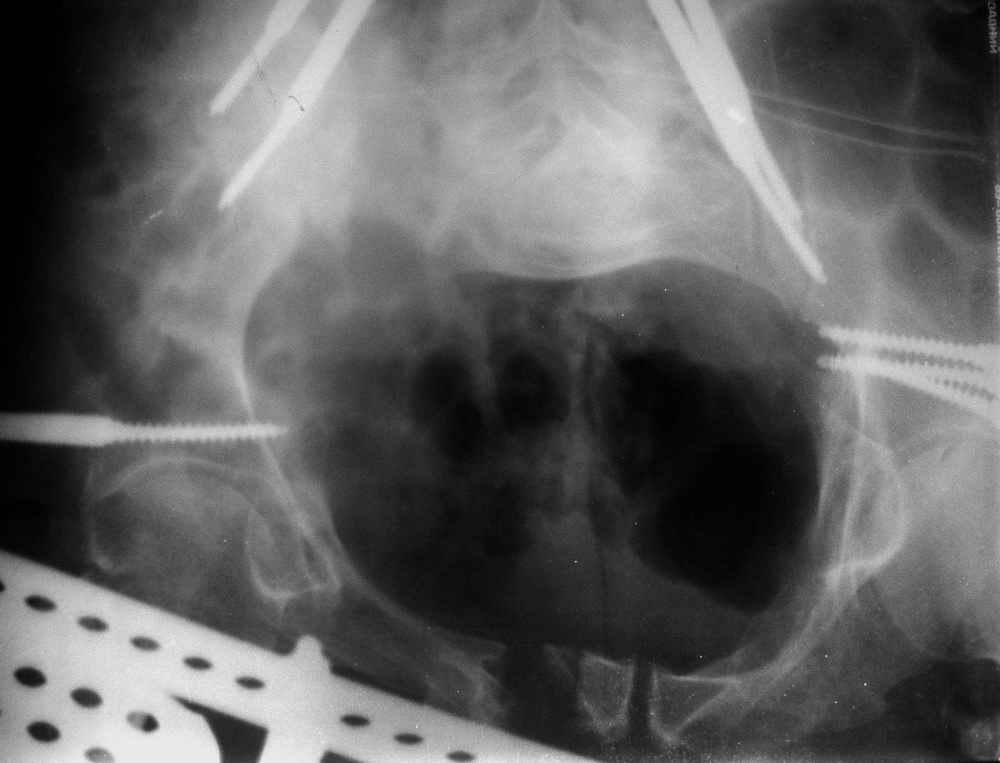

отеотомия передних и задних отделов, дистракция аппаратом